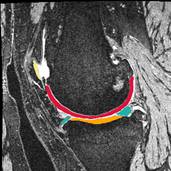

Improving Treatment for Patellar Instability to Reduce Recurrence and Cartilage Degradation

Lateral patellar instability is a traumatic event that consistently leads to cartilage damage.  Approximately 50% of patients treated for patellar instability develop patellofemoral osteoarthritis (OA) within 25 years, with a higher risk of OA for patients with recurrent instability.  The investigators have initiated this line of research to improve understanding of post-traumatic OA related to patellar instability, identify patients at greatest risk of post-traumatic OA, and optimize treatment methods to reduce the risk of OA. Quantitative MRI, statistical shape modeling and computational models will be used to provide a comprehensive evaluation of the joint structure, tissue composition and functions.